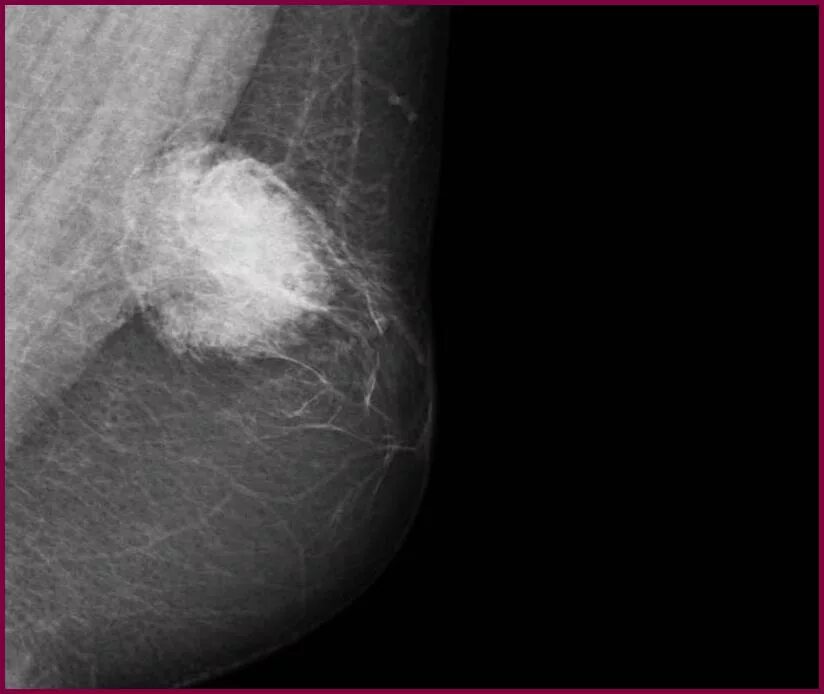

Фиброзное уплотнение молочной железы